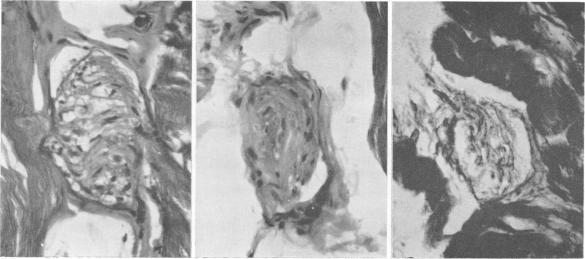

Toxic polyneuritis in Bombay due to ortho-cresyl-phosphate poisoning.

J Neurol Neurosurg Psychiatry. 1962 Aug;25(3):234-42. doi: 10.1136/jnnp.25.3.234.